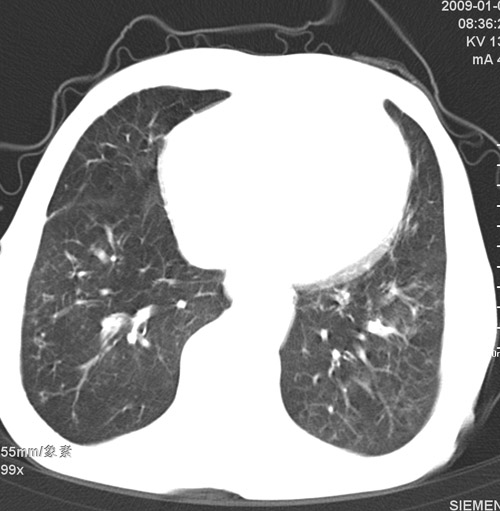

标题: CT17529:男 76 胸背部不适半月 胸透支气管炎 行CT检查 [打印本页]

标题: CT17529:男 76 胸背部不适半月 胸透支气管炎 行CT检查

意见 老年肺 少许炎症 肺大泡 右肺门略大 但支气管通畅  请各位高手指教如何下意见

间质纤维化伴少许炎症!另:肺大泡形成!

支持楼主意见,右肺门略大,可能为肺动脉增粗.

慢支肺气肿,肺动脉高压.